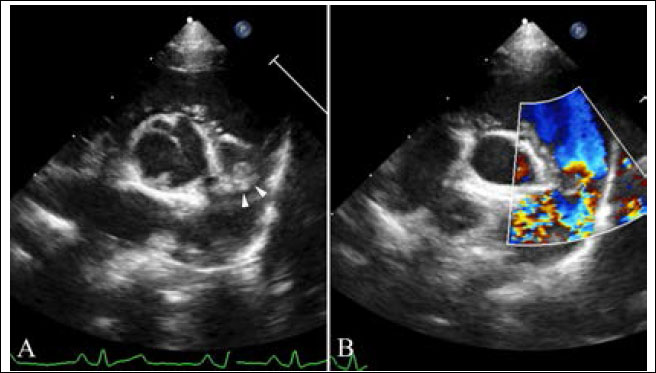

In the main pulmonary artery, there was abnormal discrete tissue approximately 7.0 mm away from the pulmonary valve, consistent with a supravalvular stenotic lesion. Color flow and continuous-wave Doppler showed turbulent blood flow originating at the level of the stenotic lesion with a 3.8 m/second peak velocity (57 mmHg pressure gradient). No marked post-stenotic dilation of the main pulmonary artery was observed (Fig. 3, Supplementary Video II). The right atrium and ventricle were normal in size and appearance.

Fig. 3. Echocardiography of right parasternal short axis view showing the right ventricular outflow tract. (A) The supravalvular lesion (arrowheads) is shown distal to the pulmonary valve. (B) color flow Doppler ultrasound shows turbulent blood flow originating at the level of the supravalvular stenotic lesion.